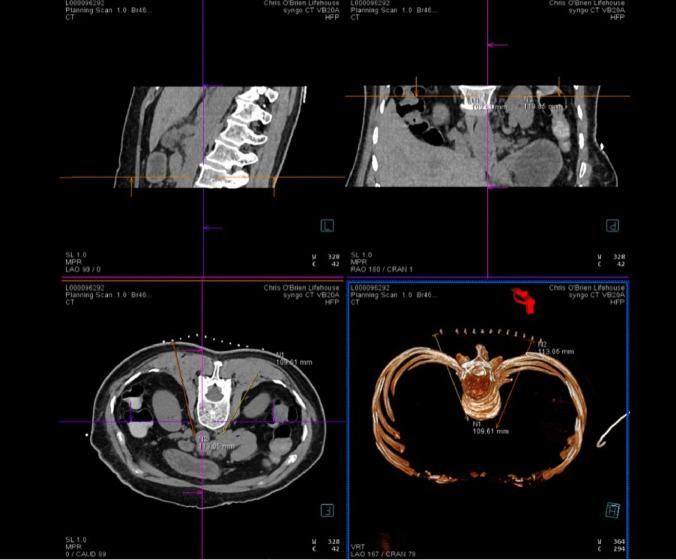

The use of interventional procedures for cancer pain. A brief review.

In this paper we discuss the interventional pain procedures used to treat cancer pain at two major tertiary centers in Australia.

This expert review provides practical insights on cancer pain management from healthcare providers in different specialties. These insights can be used to guide the management of a wide range of cancer pain types.